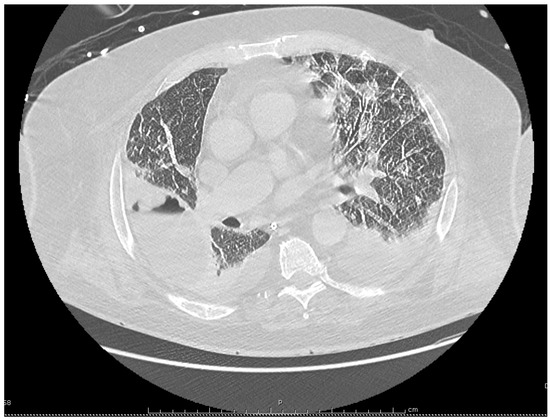

Introduction: Legionella micdadei are gram-negative bacilli living in soil and aquatic habitats. They are responsible for less than 10% of legionellosis, but have a propensity to affect people suffering from immunodeficiency. Lung cavitations may also occur in this population. Isolation of L. micdadei on clinical samples requires specific culture media that are not routinely used. Moreover, serologic methods and urinary assays are specific for Legionella pneumophila serogroup 1 (the most frequent serogroup isolated from clinical specimens), and lack sensitivity for diagnosing L. micdadei infection. As a consequence, this diagnosis is difficult to confirm. Case report: We report here a severe case of community-acquired legionellosis due to L. micdadei, in a patient under immunosuppressive medications and high-dose corticosteroids for rheumatoid arthritis. The source of his infection was hypothesized to be his continuous positive airway pressure device, which was regularly cleaned with tap water instead of sterile water, thus potentially resulting in Legionella contamination. Conclusions: L. micdadei must be considered as a possible cause of community-acquired severe pneumonia in case of immunodeficiency. For outpatients, advice concerning the cleaning of aerosols-generating devices at home must be emphasized. Full article